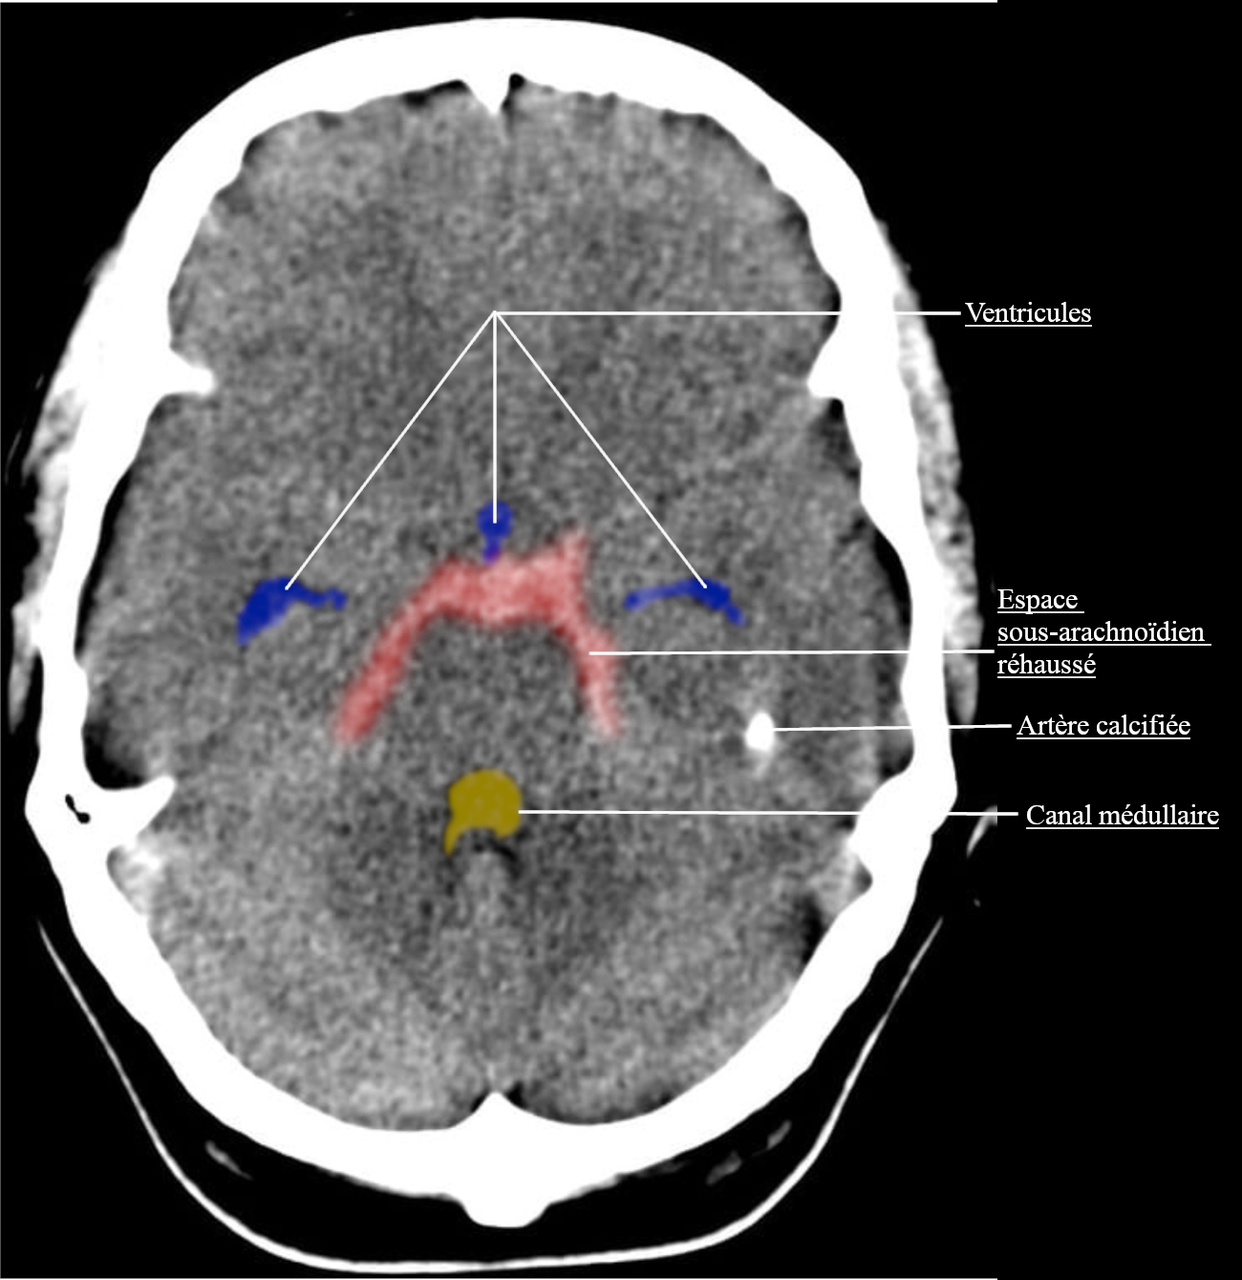

L’hémorragie sous-arachnoïdienne (HSA) a une symptomatologie qui est très importante à connaître, pour les ECNi comme pour la pratique. On retrouve une céphalée BRUTALE, d’emblée maximale (une heure précise d’arrivée est un signe évocateur).